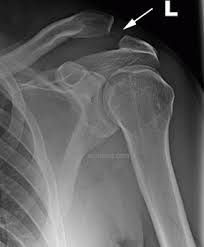

Shoulder separation (AC separation) is a common injury that occurs when the collarbone separates from the upper part of the shoulder blade (acromion). The acromioclavicular joint (AC joint) is where the clavicle meets the highest point of the acromion. Shoulder separation typically occurs when the arm is forcefully twisted outward while above the shoulder, tearing the acromioclavicular and the coracoclavicular (CC) ligaments. These shoulder injuries often occur as a result of falling, a direct blow to the shoulder, or lifting heavy objects. AC separations are common in direct contact sports, such as football and hockey, but can occur in various situations at any age. A shoulder can become partially dislocated (subluxation) or completely dislocated, in which the ball of the arm comes completely out of the socket.